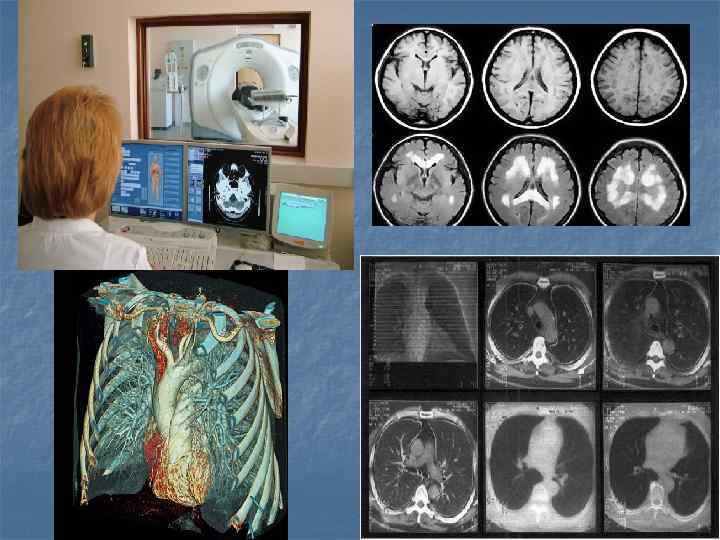

Показания n n Опухоли и метастазы Кисты, абсцессы и паразитарные кисты Сочетанная травма Воспалительные процессы(пневмония, селликозы, гепатиты, артрозы)

Показания n n n n Заболевания головного мозга, 2. Исследования функций отделов головного мозга, 3. Заболевания суставов, 4. Заболевания спинного мозга, 5. Заболевания внутренних органов брюшной полости, 6. Заболевания системы мочевыведения и воспроизводства, 7. Заболевания средостения и сердца, 8. Заболевания сосудов.

Показания При заболеваниях головного мозга показания к МРТ следующие: инфаркты, инсульты – для оценки масштабов поражения мозга; рассеянный склероз; дегенеративные и демиелинизирующие патологии нервной ткани; нарушения работы гипофиза; инфекционные заболевания (энцефалит и пр. ) n Магнитно-резонансная томография успешно используется для выявления патологий сосудистого русла: тромбы, аневризмы; артерио-венозные мальформации; стеноз; окклюзии; n При обследовании позвоночника имеются следующие МРТ показания: кровоизлияния в спинной мозг; стеноз позвоночного канала; компрессии спинного мозга; протрузии, грыжи межпозвоночных дисков; воспалительные заболевания спинного мозга и позвоночника; сосудистые нарушения, спинальный инсульт. n При патологиях суставов томография позволяет определить: воспалительные и инфекционные заболевания; артриты, бурситы, артрозы; дегенеративно-дистрофические изменения. n При обследовании органов грудной клетки, брюшной полости, забрюшинного пространства, малого таза метод используется для выявления: врожденных и приобретенных пороков сердца; заболеваний грудной, брюшной аорты и других сосудов; абсцессы, гематомы, воспалительные поражения печени, почек, селезенки и других органов; желчнокаменной болезни; нарушений лимфатической системы; повреждения органов после травм; инфекционные и прочие нарушения. n